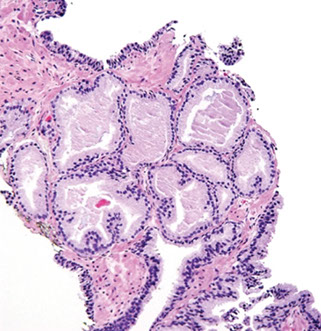

Ductal Adenocarcinoma

Hard to diff HG-PIN and ductal AC

- ductal ACs are agressive, advanced stage, and assoc c a poor px

- critical to diff from PIN

- ductal AC usually centrally located in periurethral region and sampled on TURP

-- PIN uncommon in periurethral region and infreq seen on TURP

- ductal AC usually has true papillary fronds c well-formed fibrovascular core, whereas HG-PIN more freq reveals micropapillary fronds c tall columns of epithelium w/o fibrovascular stalks

- ductal AC freq has comedonecrosis, which can be extensive

-- HG-PIN lacks comedonecrosis

- ductal AC can consist of large or back-to-back glands, whereas glands c PIN are of the size and distribution of b9 glands

- use of basal cell markers in the DDx can be problematic as both HG-PIN and ductal AC can have a patchy basal cell layer, however, the lack of a basal cell layer in numerous glands rules out PIN

Although the MC forms of ductal AC mimic cribriform and micropapillary HG-PIN, ductal AC can be composed of simple glands lined by stratified columnar epithelium c cytologic and architectural features of flat and tufting HG-PIN

- these PIN-like ductal cancers are distinguished from HG-PIN either bc the atypical glands are too crowded to represent HG-PIN or there are too many atypical glands that are negative for basal cell markers to be consistent with HG-PIN

- additional differences are in the PIN-like ductal AC, many of the glands are lined by flat epithelium (an uncommon pattern in HG-PIN) and the glands are often cystically dilated

Px: up to 1/2 metastatic at dx

Ductal AC